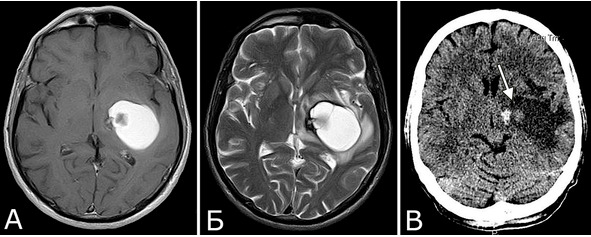

Критерии диагноза. Вопрос о правомерности и критериях диагноза «кровоизлияние из каверномы» долгое время являлся предметом оживленной дискуссии. Помимо академического интереса, эта проблема важна в связи с тем, что частота кровоизлияний является одним из основных факторов при определении показаний к хирургическому вмешательству, а также при оценке и сопоставлении эффективности различных методов лечения, в особенности, при оценке результатов радиохирургии. Существует два различных подхода к установке диагноза «кровоизлияние». Согласно первому, диагноз можно считать обоснованным только в случаях выявления свежей крови при КТ, МРТ или люмбальной пункции (227, 278, 294) – это так называемые доказанные, или очевидные (overt) кровоизлияния. Однако, рентгенологическая, а тем более, ликворологическая верификация кровоизлияния возможна далеко не всегда. Для подтверждения факта кровоизлияния по КТ или МРТ необходимо, чтобы оно было достаточно массивным. Кроме того, обследование должно быть проведено в ближайшие сроки после появления соответствующей симптоматики, что выполняется достаточно редко, особенно в случаях небольших кровоизлияний. В остром и подостром периоде кровоизлияния, особенно достаточно объемного, может быть выявлен перифокальный отек, хотя выраженный отек в целом не характерен (рис. 35).

Рис. 35. Кавернозная мальформация правой височной доли с небольшим перифокальным отеком, 17-е сутки после кровоизлияния. А, Б – МРТ, режимы Flair, Т2